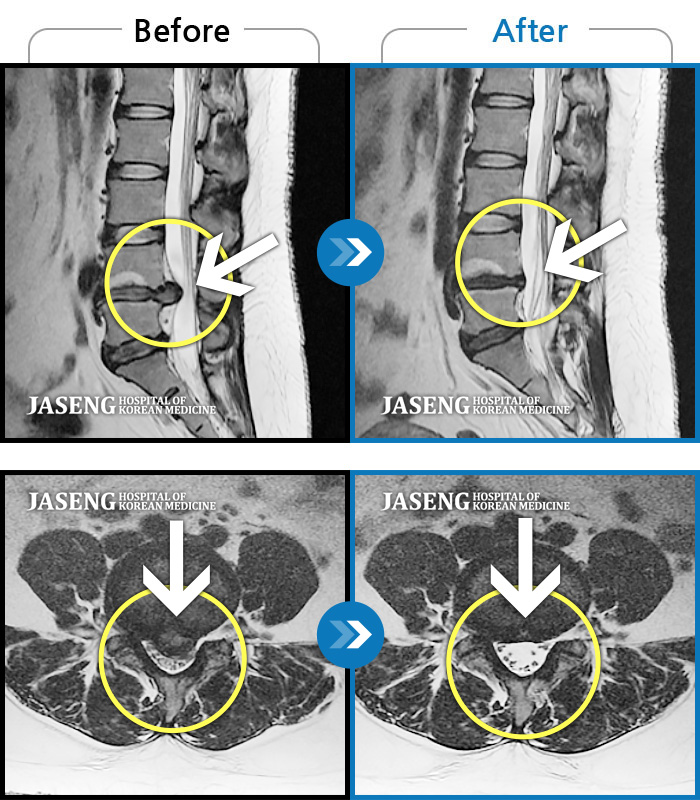

MRI 치료사례

요추 4,5번 급성 허리디스크